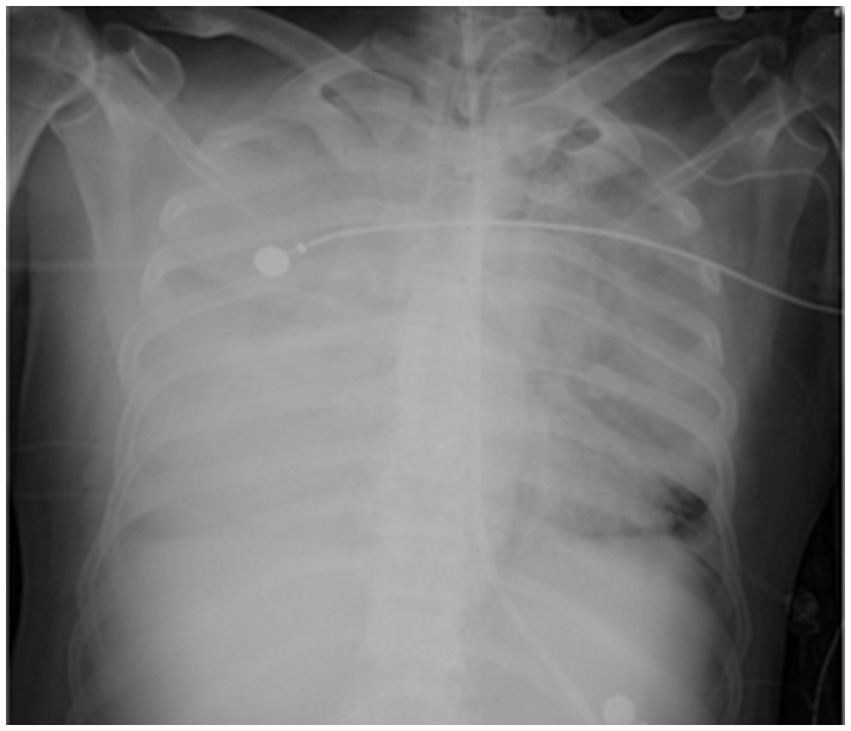

On the sixth day following VV-ECMO treatment, a favorable outcome was observed as the sputum culture yielded negative results (IL-6: 100 pg./mL, CRP: 195 mg/L), and there was a significant decrease in inflammatory indicators. The patient’s pulmonary condition demonstrated a marked improvement relative to the previous state, prompting a change in the antibiotic regimen to cefoperazone sodium-sulbactam sodium (2 g) administered every 8 h and voriconazole (200 mg) given via nasogastric feeding every 12 h. Concurrently, the patient’s oxygenation index improved, and lung function gradually recovered. This was based on the patient’s improved oxygenation and gradually recovering lung function, which indicated that the patient might be able to tolerate the discontinuation of ECMO support. The ECMO parameters were gradually titrated downwards, and the ECMO was weaned on the ninth day post-VV-ECMO treatment. At this point, the lung condition has improved significantly compared to before (Figure 2, and IL-6: 53 pg./mL, CRP: 202 mg/L). Given the patient’s persistent difficulty with extubation, the presence of retained respiratory secretions was suspected. Thus, percutaneous tracheotomy was performed on the second day post-ECMO weaning to alleviate the patient’s dyspnea symptoms. To further assess the patient’s lung condition following ECMO weaning, a repeat chest CT scan was performed on the fourth day after the procedure. The imaging revealed the emergence of new local masses with cavitation in the middle lobe of the right lung and the upper lobes of both lungs. This was suspected to be lipoid pneumonia with local lung tissue necrosis. Additionally, bilateral pleural effusion was noted, and the pneumonia had progressed compared with the previous state (Figure 3, and IL-6: 3557 pg./mL, CRP: 316 mg/L). Limited empyema was suspected, and the surgical department determined that the patient had indications for lung transplantation. However, the family members declined the surgery due to financial constraints. On the seventh day following ECMO weaning, the patient again exhibited hypotension, tachypnea, and tachycardia. Bedside chest X-ray suggested progression of exudation and consolidation in both lungs, along with bilateral pleural effusion (Figure 4, and IL-6: 5938 pg./mL, CRP: 322 mg/L). Septic shock secondary to pneumonia complicated by infection was suspected. Linezolid, at a dosage of 600 mg administered every 12 h, was added to the treatment regimen. Since the patient’s family members refused re-ECMO treatment, the deteriorating lung condition could not be reversed. On the ninth day post-ECMO weaning, the patient experienced cardiac arrest. Immediate bedside resuscitation was initiated. One minute later, the carotid artery pulsation ceased, and chest compression was terminated. The patient was declared clinically dead (The fluctuation of the patient’s oxygenation index can be observed in Figure 5, and the treatment route can be seen in Figure 6).

Figure 2

Figure 2. Lung CT on the day of ECMO weaning.